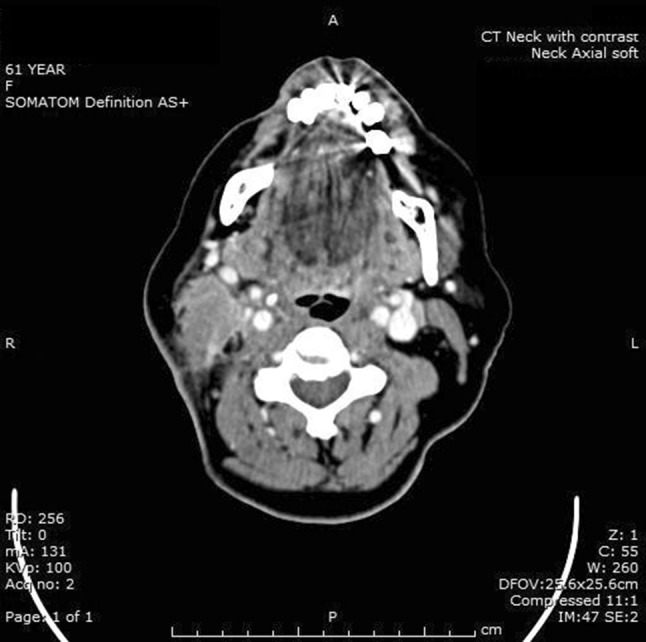

A 61 year old lady, with a background of type 2 diabetes mellitus and chronic obstructive pulmonary disease, was referred to the Otolaryngology department from her General Practitioner (family medicine practitioner) with a 4 week history of a right sided inferior neck mass. She had a mild feeling of general malaise and examination of the mass was consistent with a level 5 neck abscess, with corresponding level 2 and 5 lymphadenopathy. The remainder of head and neck examination, including flexible nasendoscopy, was unremarkable. Aspiration of the lump was attempted on first presentation to ENT, but was unsuccessful in yielding any fluid. Blood tests showed both white cell count and C-reactive protein to be within normal ranges at first presentation. She was treated with Co-amoxiclav, which initially gave a mild improvement in her symptoms, but the lump never completely resolved and her symptoms recurred rapidly after stopping the antibiotics. Several further prolonged courses of antibiotics were used, with similar results. After several months, the wound began to discharge purulent material and some granulation tissue was apparent around the wound site (Fig. 1). Multiple swabs of the wound and discharge were taken for culture, but none grew any organism. Tuberculosis was queried, but Ziehl-Neelsen staining and prolonged culture for Mycobacteria were negative. Initial core biopsy samples were reported as showing chronic inflammatory tissue. A contrast enhanced CT scan of the neck (Fig. 2) showed appearances consistent with an inflammatory mass encircling the right sternocleidomastoid muscle with a central fluid component and overlying skin thickening.

Contrast enhanced CT scan showing a right sided inflammatory neck mass

Fig. 2.